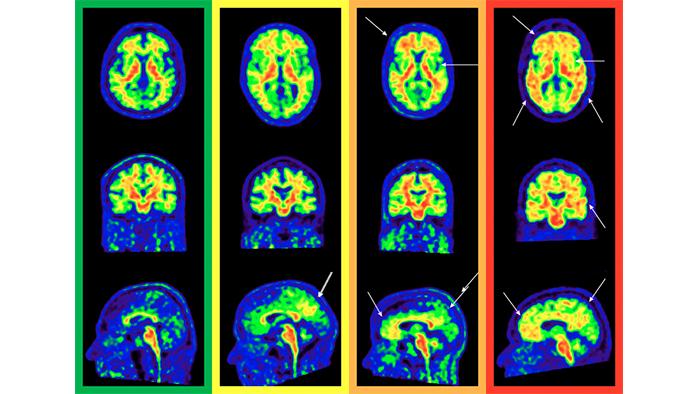

Investigadores europeos mejoran la sensibilidad del diagnóstico de las fases iniciales del Alzheimer